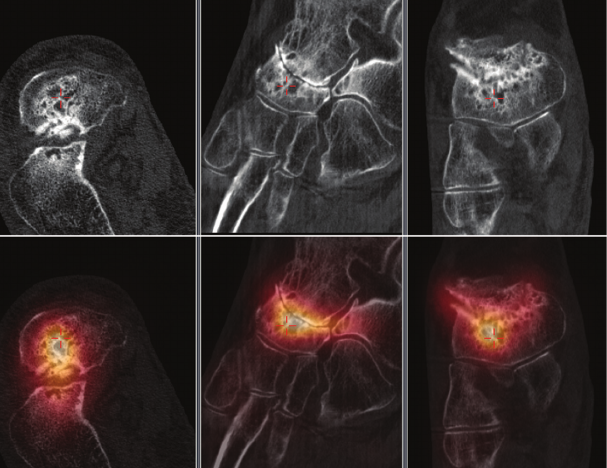

to patient management. Figure 1 shows an example

where a patient was treated appropriately for

inammatory arthropathy of the right talonavicular

joint rather than incorrectly for a stress fracture which

may not have been appreciated without SPECT/CT.

Figure 1 Tc-99m HDP SPECT/CT study performed on an 80-year-old patient with severe

ankle pain and suspected stress fracture. BrightView XCT exam reveals markedly increased

vascularity and delayed uptake in the hind foot and demonstrated intense uptake in right

talonavicular region with severe degenerative change on low dose CT (subarticular cyst

formation, joint narrowing and periarticular sclerosis).

Clinical data courtesy of Sydney X-Ray, Sydney, Australia